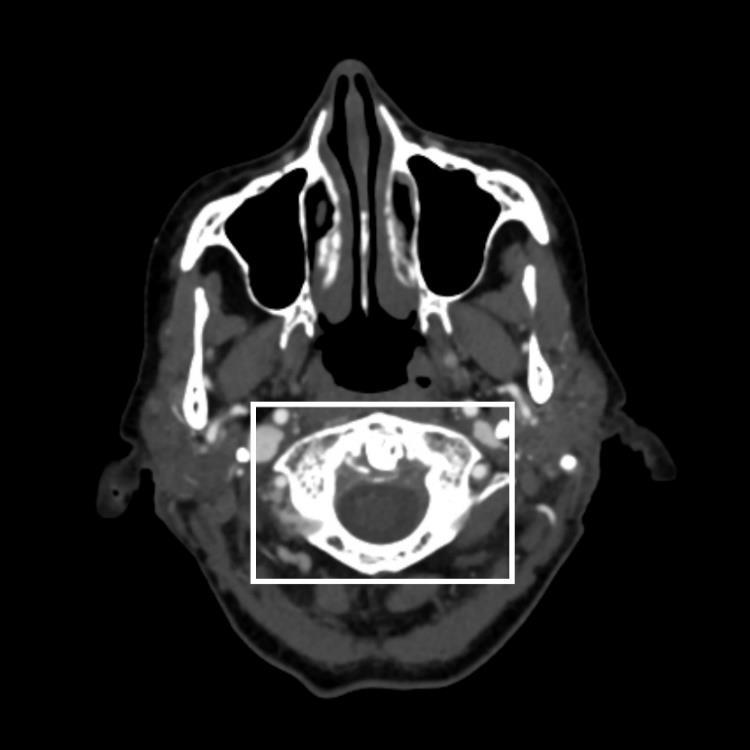

381 A Diagnosis Fit for a Queen: Crowned Dens Syndrome

10.SnyderAandSchmalzleSA.Spontaneous Streptococcuspyogenes pelvicinflammatorydisease;casereportandreviewoftheliterature. IDCases. 2020;20:e00785.